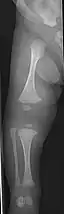

Diagnosis is typically based on medical imaging, including plain X-rays, and symptoms. In severe OI, signs on medical imaging include abnormalities in all extremities and in the spine.[97] As X-rays are often insensitive to the comparatively smaller bone density loss associated with type I OI, DEXA scans may be needed.[5]: 1514

An OI diagnosis can be confirmed through DNA or collagen protein analysis, but in many cases, the occurrence of bone fractures with little trauma and the presence of other clinical features such as blue sclerae are sufficient for a diagnosis. A skin biopsy can be performed to determine the structure and quantity of type I collagen. While DNA testing can confirm the diagnosis, it cannot absolutely exclude it because not all mutations causing OI are yet known and/or tested for.[83]: 491–492 OI type II is often diagnosed by ultrasound during pregnancy, where already multiple fractures and other characteristic features may be visible. Relative to control, OI cortical bone shows increased porosity, canal diameter, and connectivity in micro-computed tomography.[98] OI can also be detected before birth by using an in vitro genetic testing technique such as amniocentresis.[99]